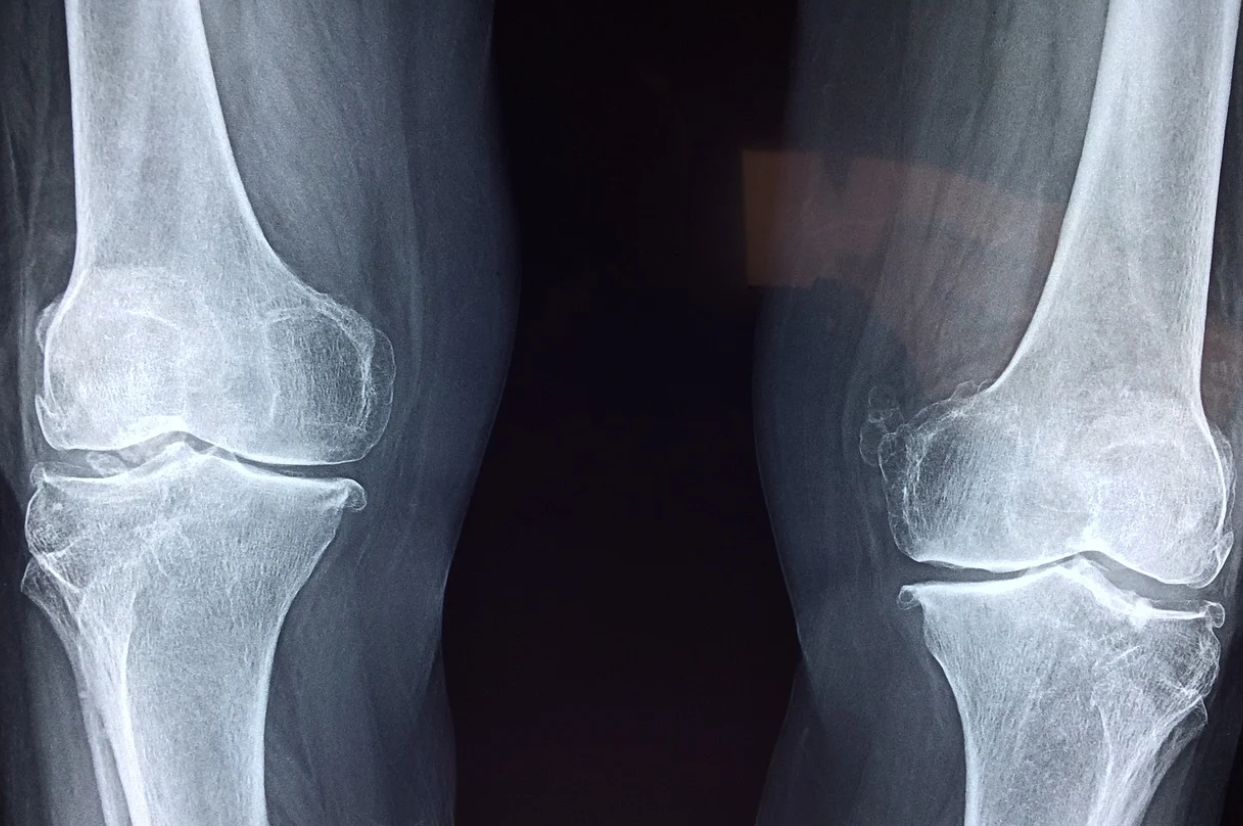

대부분의 근골격계질환은 외상적 진단이 불가능한 경우가 많고 조기발견도 어렵다. 심한 경우가 아니면 통증이 있다가 없다가를 반복한다. 그래서 곧 괜찮아지겠지 라는 생각하다가 질환이 심해질 수 있다. 완치가 안된 상태에서 작업복귀를 하다가 다시 재발하고 그러다보니 완치가 어려운 질환이다.

조기발견이 어렵고 개인적으로 참으며 작업을 하다가 완치가 어려워 심하면 장애가 생길 수 있는 질환이다.

그러니 사업장 작업환경에 대한 개선활동뿐 아니라 작업속도, 휴식시간, 직무스트레스 등 다양한 관점에서 복합적인 예방 노력이 필요하다고 생각된다.